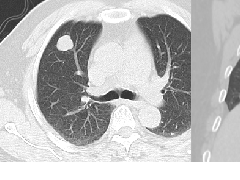

粘液腺癌影像上分为:结节型及斑片型/混合(肺炎型)。

一、结节型粘液腺癌和普通腺癌类似,重视体检及复查不易遗漏

1.多位于胸膜下,90%位于胸膜下,70%下叶胸膜下(125例)

2.病变周围GGO,边界清楚或稍模糊。圆圈征、草帽征、树上蘑菇征等。

3.结节型发展缓慢,淋巴结转移少见。